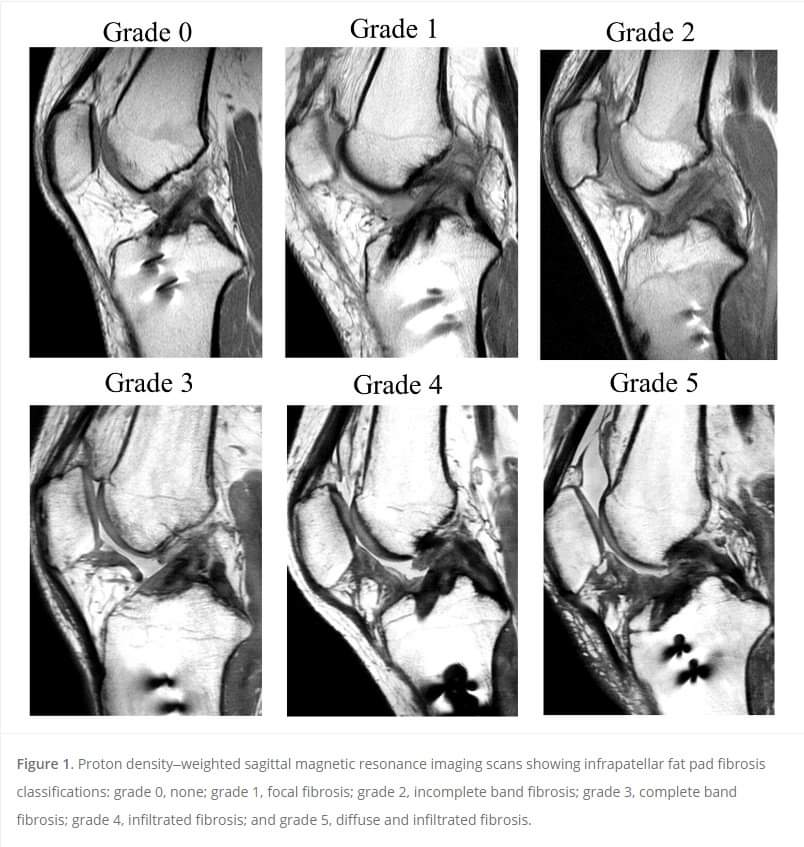

Physiotherapy clinic in Tambaram Are you Looking for Physiotherapy Treatment in Tambaram, Sunshine Super Speciality Physiotherapy Clinic, We Provide Electrotherapy, Exercise and Manual Therapy, Orthopedic, Neuro, Cardio, Pediatric, Sports and Geriatric Rehabilitation, Post Operative Physiotherapy Treatment, Fracture Rehabilitation, pain free movement. Continued anterior knee pain after ACL reconstruction (ACLR) may be due to infrapatellar fat pad (IFP) fibrosis, which is associated with a longer operation time, higher inflammatory cytokine level in the synovial fluid, and worse clinical outcomes at 3 and 12 months after ACLR. http://ow.ly/PL0p50OqyAM SUNSHINE ® SUPER SPECIALITY PHYSIOTHERAPY CLINIC - #DrParthiban #Sunshinephysioclinic.in #Physiotherapyclinicintambaram DR.M.P. PARTHIBAN.M.P.T (Ortho), Chief Orthopedic Physiotherapist, Call for Appointments: - 9345122177 East Tambaram, CHENNAI